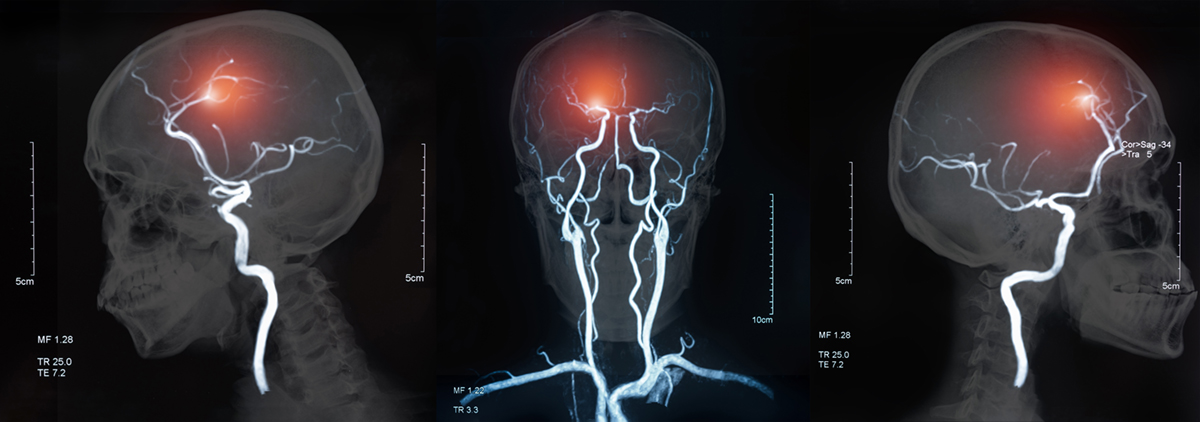

以上の実験から川上博士は、

腸閉塞が起こった際、一種の毒素が生成され、これが脳に伝わって脳の血管を破るか、膨張するか、麻痺するかする。

そして腸閉塞に陥らせるものは便秘であり、停滞便(宿便)である。

と結論しています。

これはあくまで動物実験ですから、必ずしも人間も同様だとは言い切れません。

しかし、わたしたち人間の97.7%(成人の100%)という、ほとんど全員と言ってもよいくらいの人の脳に出血を起こさせているその原因が、実は「便秘」にある可能性が示唆されたということです。

便秘 ➡︎ 宿便 ➡︎ 腸麻痺 ➡︎ 腸内腐敗(腸内異常醗酵)➡︎ 有害物質の生成 ➡︎ 毒性血液の全身大循環 ➡︎ 慢性自家中毒のメカニズムは、脳にも及び、脳出血をも引き起こす可能性があるということです。